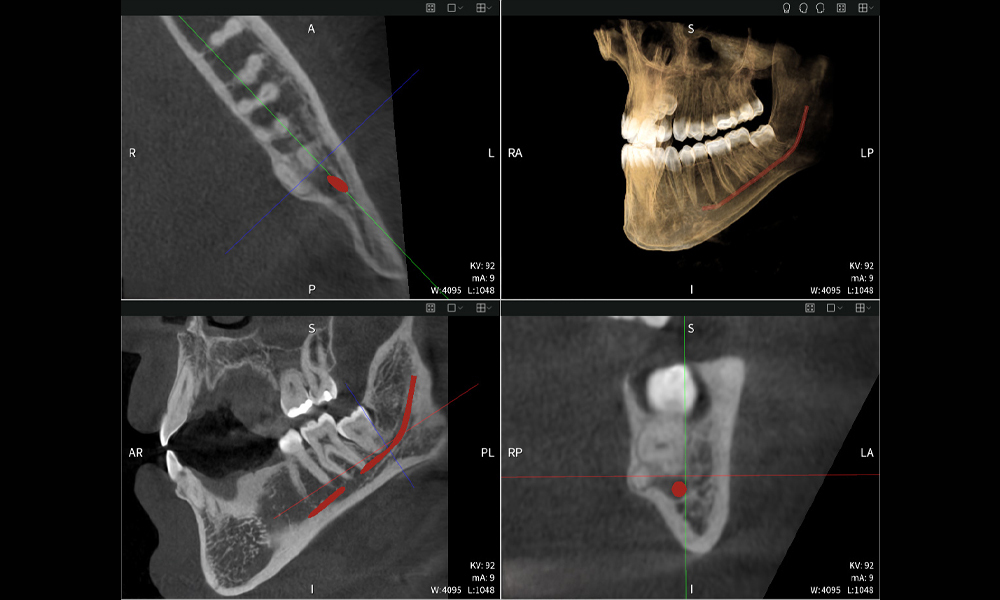

Below you will find a case from Dr. med. dent. Oliver A. Centrella, in which the CBCT images obtained with Seethrough Max provided crucial information on the complex anatomy and the critical relationship between the wisdom teeth and the inferior alveolar nerve. In this case, there is a indication for the surgical removal of the wisdom teeth.

Figure a: Imaging results of Seethrough Max, in front of a black background.

Figure a

• Top left: Axial cross-section of the left mandible (region 38) showing the inferior alveolar nerve (red) in proximity to the roots of tooth 38.

• Top right: 3D reconstruction of the entire mandible for orientation. The red-marked inferior alveolar nerve illustrates its location within the jawbone.

• Bottom left: Sagittal view of the mandible (region 38), highlighting the close spatial relationship between the roots and the nerve canal.

• Bottom right: Coronal view of the mandible (region 38), which is crucial for assessing the spatial position of the roots relative to the nerve.